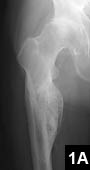

An uncommon, but useful indication for hip resurfacing is for patients with proximal femoral deformity, in whom a total hip can be difficult if not impossible (Figure 1). More commonly, suboptimal anatomy is an issue, as with patients in whom even the smallest stem requires reaming, which puts patients at long-term risk for stem fracture (Figure 2). Conversely, a large canal presents problems for implanting a cementless stem (Figure 3).

Figure 2: Preoperative templating of a 38-year-old dancer reveals the smallest standard stem available would still require reaming of cortical bone (A). Postoperative radiograph shows successful hip resurfacing was performed without entering the femoral canal (B).